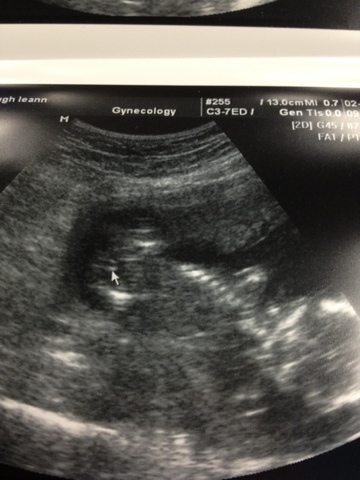

Landry: 17 week & shot update

I had my 16 weeks appointment yesterday and I was suppose to start my progesterone shots. That didn't happen! But first I had an ultrasound to check on Landry's growth and my cervical length. He is doing great and measuring right on track. My cervical length is at 3.6cm, which anything over 3 cm is ideal. We will be watching this very closely. I am up 2 pounds from last month and up 1 pound overall. Blood pressure was great as well at 106/68.